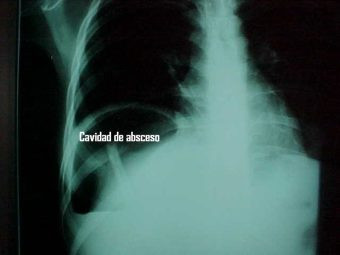

Abcseso Subfrénico

Envíado por Dr. Carlos Edgardo Escobar